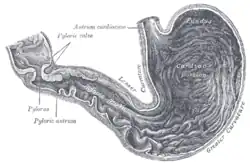

Der Pylorus (altgriechisch πυλωρός pylōrós, deutsch ‚Pförtner‘[1]), das Ostium pyloricum, der Magenausgang oder Magenpförtner ist der letzte Abschnitt des Magens zwischen dem Antrum pyloricum („Pförtner-Vorraum“) und dem Zwölffingerdarm (Duodenum). In seiner Wand bildet die ringförmig angeordnete glatte Muskulatur einen Schließmuskel, den Musculus sphincter pyloricus. Der Pylorus ist in Ruhe geschlossen. Er hat die Aufgabe, den Weitertransport des Nahrungsbreis vom Magen in den Darm zu regulieren.[2] Bei vielen Paarhufern weist der Pylorus durch Drüsen in der Submukosa und Verdickung der Ringmuskelschicht einen Wulst (Torus pylori) auf, der die Öffnung des Magenpförtners verengt.[3]

Bei leerem Magen ist der Pylorus entspannt. Die Regulierung der Öffnung und des Schlusses des Pylorus ist ein komplizierter und noch nicht in allen Aspekten verstandener Vorgang. Nicht jeder peristaltischen Welle des Magens folgt auch eine Pylorusöffnung. Der Energiegehalt der Nahrung, osmotischer Druck und pH-Wert in Magen und Zwölffingerdarm spielen dabei eine Rolle.[4] Die Magenentleerung wird dabei sowohl vom enterischen Nervensystem der Magenwand als auch vom Nervus vagus und verschiedenen Hormonen gesteuert. Flüssigkeiten und Nahrungspartikel kleiner als ein Millimeter passieren den Pylorus schnell, während gröbere Nahrungsbestandteile zurückgehalten und im Magen weiter verkleinert werden.[5]

Durch kurzzeitige Öffnung des Pylorus gelangt ein kleiner Anteil (Bolus) des Mageninhaltes (Chymus) in den Zwölffingerdarm. Der die Öffnung auslösende Pylorusreflex ist ein viszero-viszeraler Reflex, welcher den Muskel bei alkalischem (hoher pH-Wert) Chymus im Zwölffingerdarm schließt und ihn bei saurem oder fettem Chymus öffnet.[6] Gastrische Motilität bewirkt eine Leerung des Magens, während postprandiale Motilität darauf gerichtet ist, Nahrung zwischen den Mahlzeiten zurückzuhalten, um eine kontinuierliche Abgabe zu gewähren. Die gastrische Motilität spielt eine Schlüsselrolle bei den die Nahrungsaufnahme regulierenden Empfindungen von Sattheit, Hunger und Völlegefühl.[7]